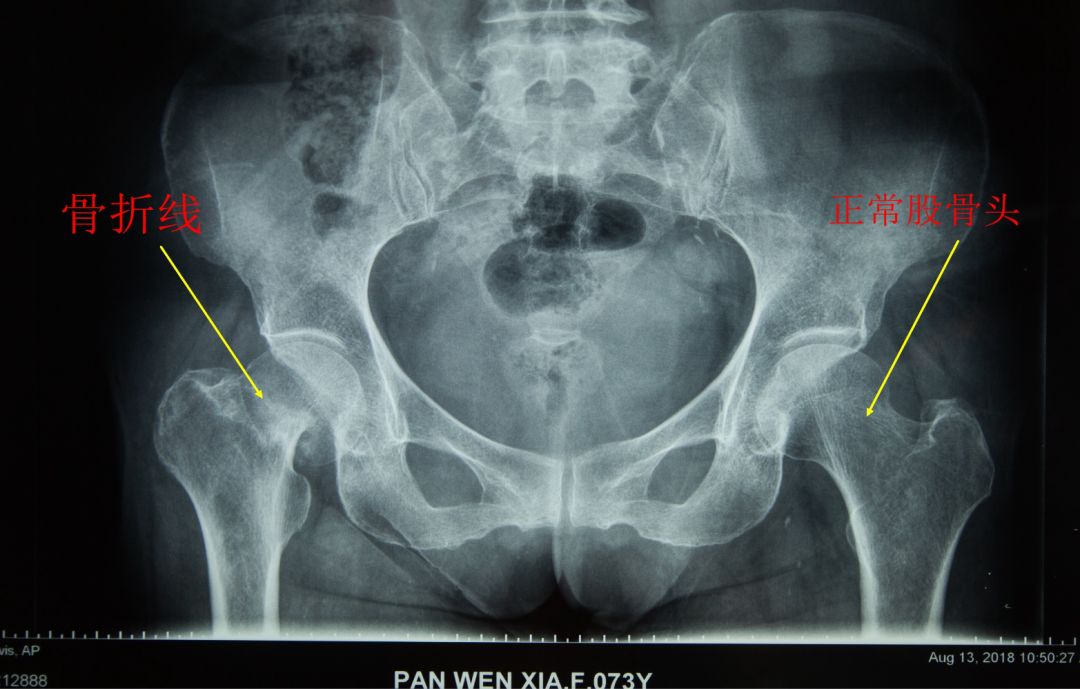

近日,生态城医院骨科王胜利主任团队顺利为一名老年女性股骨颈骨折患者进行了髋关节人工股骨头置换术。术后第三天患者开始进行下床步行器辅助行走训练,此次手术取得了满意的疗效,获得了患者及家属的一致好评,目前患者已拆线出院。

老年股骨颈的骨折被业内人士称为“老年人的最后一次骨折”。股骨颈局部血运差,骨折难以愈合,长期卧床容易给老年患者带来坠积性肺炎、泌尿系感染、深静脉血栓、褥疮等一系列并发症,并最终导致患者的死亡,会给患者及家庭带来极大的损失。

术前

术后

(圈内为骨关节假体)